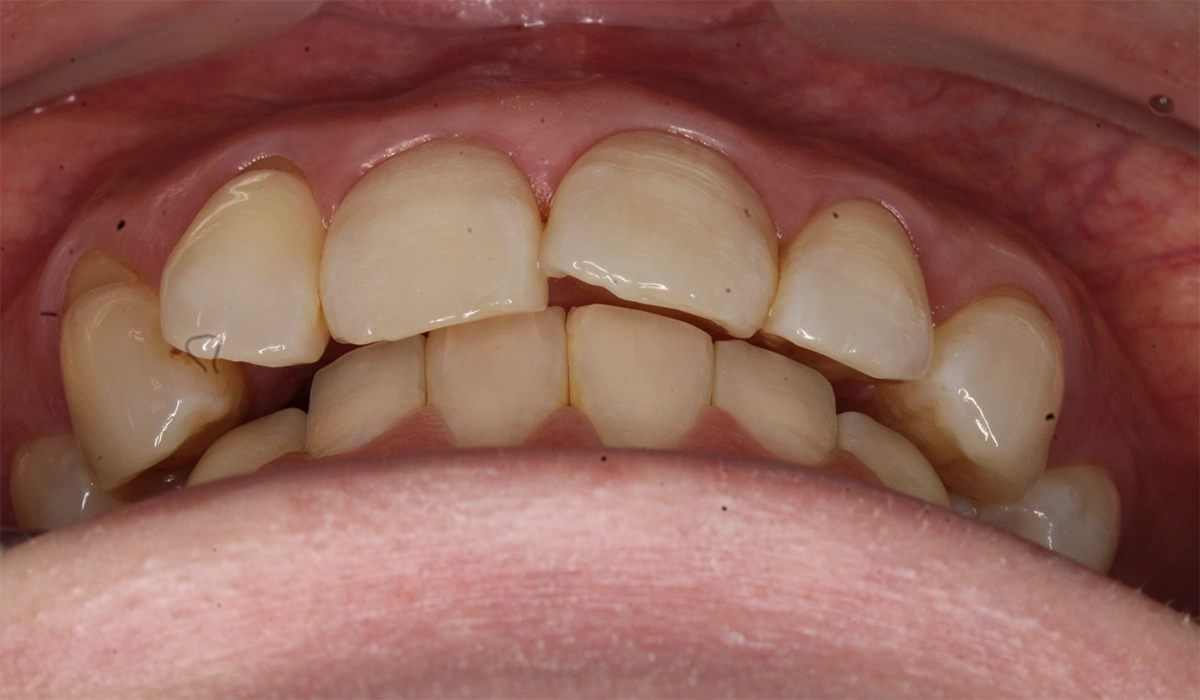

術前:前歯部あおり

主訴 前歯の捻じれが気になる

治療期間 10カ月

治療費用 550,000円(税込)

治療内容 前歯の捻じれを気にされており、矯正検査後叢生Ⅰ級と診断いたしました。